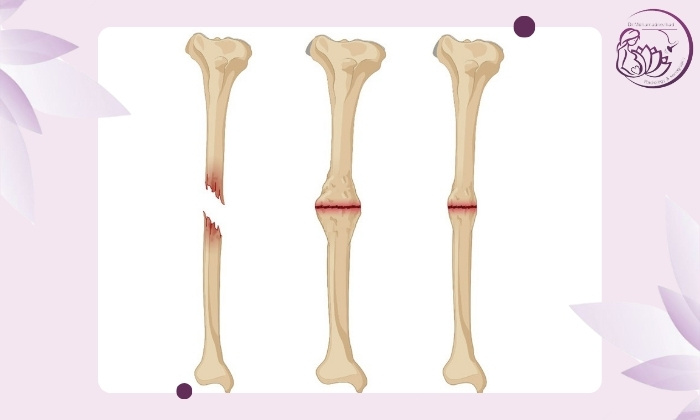

شکستگی استخوان‌ها یکی از شایع‌ترین آسیب‌های اسکلتی است که معمولاً با درمان مناسب در مدت‌زمان مشخصی ترمیم می‌شوند. اما گاهی این روند طبیعی ترمیم مختل شده و استخوان‌ها به‌درستی به هم جوش نمی‌خورند. این وضعیت که با عنوان «استخوان جوش نخورده» یا Nonunion شناخته می‌شود می‌تواند پیامدهای جدی برای سلامت، عملکرد حرکتی و کیفیت زندگی بیمار داشته باشد. در ادامه نشانه های این مشکل را بررسی می‌کنیم:

این مشکل می‌تواند دلایل مختلفی داشته باشد که معمولاً به شرایط بدن بیمار، نوع شکستگی و روند درمان

شدت و نوع شکستگی

برخی شکستگی‌ها ذاتاً ریسک بیشتری دارند:

شکستگی‌های باز

شکستگی‌های چندتکه یا خردشده

شکستگی‌های همراه با آسیب بافت نرم

شکستگی‌های ناشی از تصادفات شدید